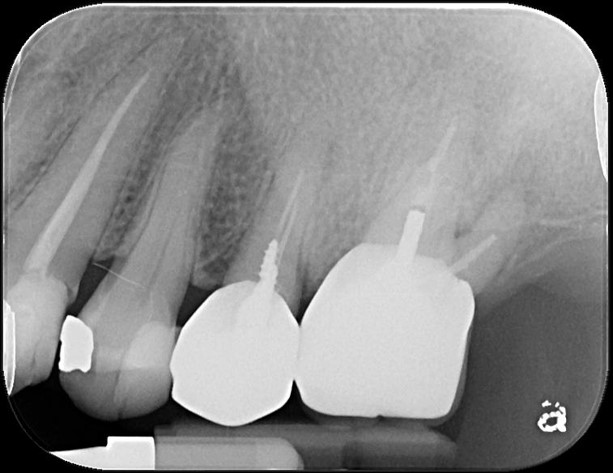

治療前,第一大臼齒根尖病變

顯微根管重治療

鑄造金屬釘柱